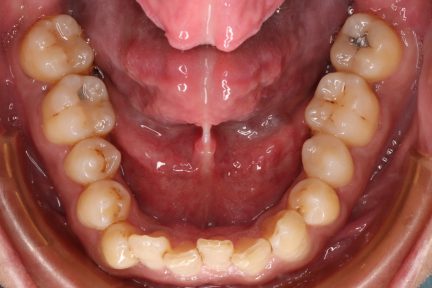

Classe I, articulation profonde, arcades étroites, arcades asymétriques, déviation de la ligne médiane mandibulaire, décalage de la ligne médiane, chevauchement, rotations

Courbe de Spee nivelée, égression, ingression, expansion, vestibulo-version

État initial